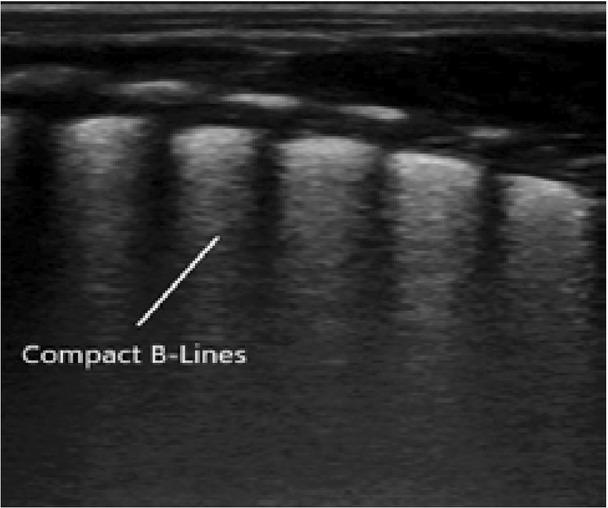

Fig. 2